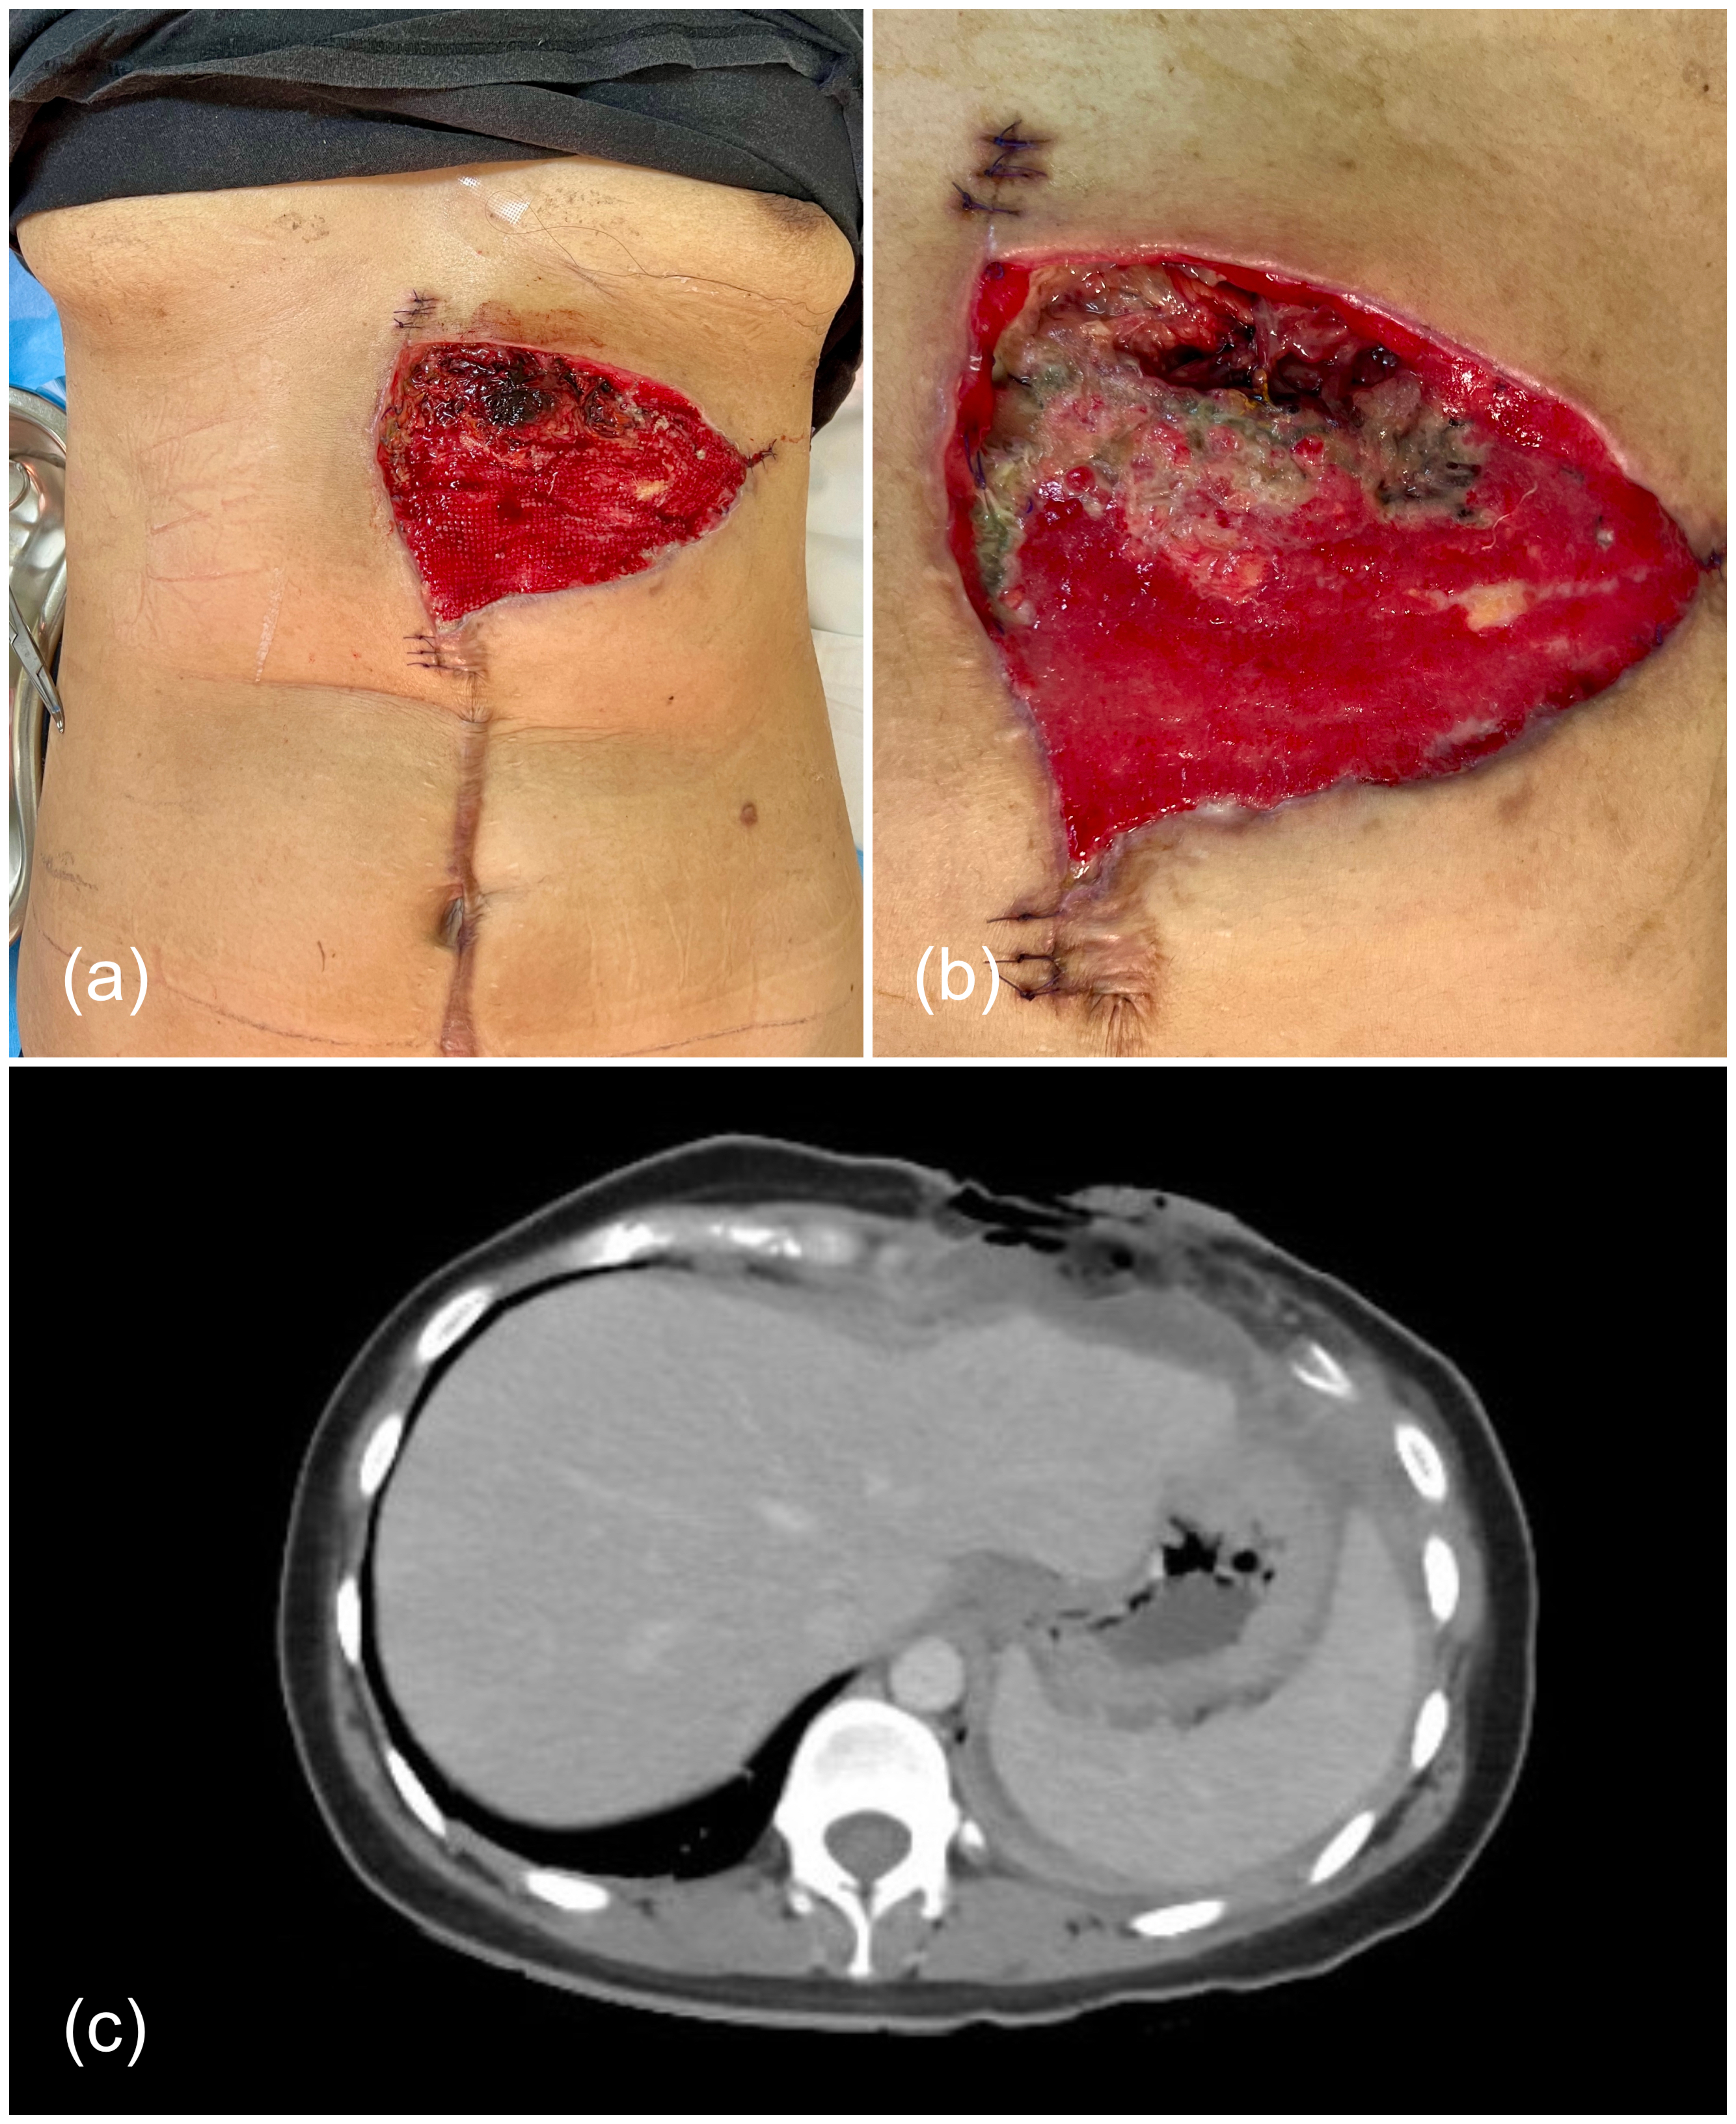

A 34-year-old female patient with history of resection of an abdominal wall desmoid tumor and reconstruction with a component separation technique presented 12 months after surgery reporting pain adjacent to the surgical site, which was ultimately determined to be a local recurrence. The resection of the recurrence included the tumor (approximately 12 × 10 × 10 cm), skin, the cartilaginous sections of the seventh and eighth left costal arches, omentum left anterior leaflet of the diaphragm, and the medial half of the right rectus abdominis muscle (Figure 1). The abdominal wall defect was reconstructed by placing a 15 × 18-cm 2-component mesh fixed to the aponeurosis. In addition, a small defect was created at the superior edge of the mesh, through which a pedicled omentum flap was exteriorized. Four weeks later, the patient developed mesh exposure and peritoneal-cutaneous communication (Figure 2).

Figure 2. Three weeks after secondary reconstruction with a 2-component mesh fixed to the surrounding aponeurosis and an exteriorized pedicled omentum flap, the patient developed partial necrosis of the flap (A), with mesh exposure and, ultimately, peritoneal-cutaneous communication (B, C).